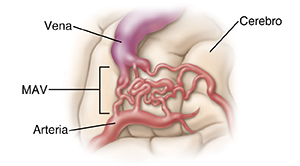

Malformación arteriovenosa (MAV)

A usted le han informado que tiene una malformación arteriovenosa (MAV). Una MAV consiste en un enmarañamiento anormal de vasos sanguíneos que causa conexiones irregulares entre las arterias y las venas en el cerebro. Algunas MAV no se rompen nunca. Pero existen factores de riesgo que pueden causar la ruptura. Algunos factores son conocidos, como un aumento en la presión arterial. Otros factores son desconocidos. Si tiene una MAV, probablemente es de nacimiento. La mayoría de las personas no sabe que la tiene hasta que aparece un problema. Entre los síntomas de la MAV se encuentran los siguientes: dolores de cabeza fuertes, pérdida de la sensibilidad o parálisis repentina o progresiva, vista nublada o doble, y ataques convulsivos (movimientos y sacudidas descontrolados).

¿En qué consiste una MAV?

El problema con el flujo sanguíneo